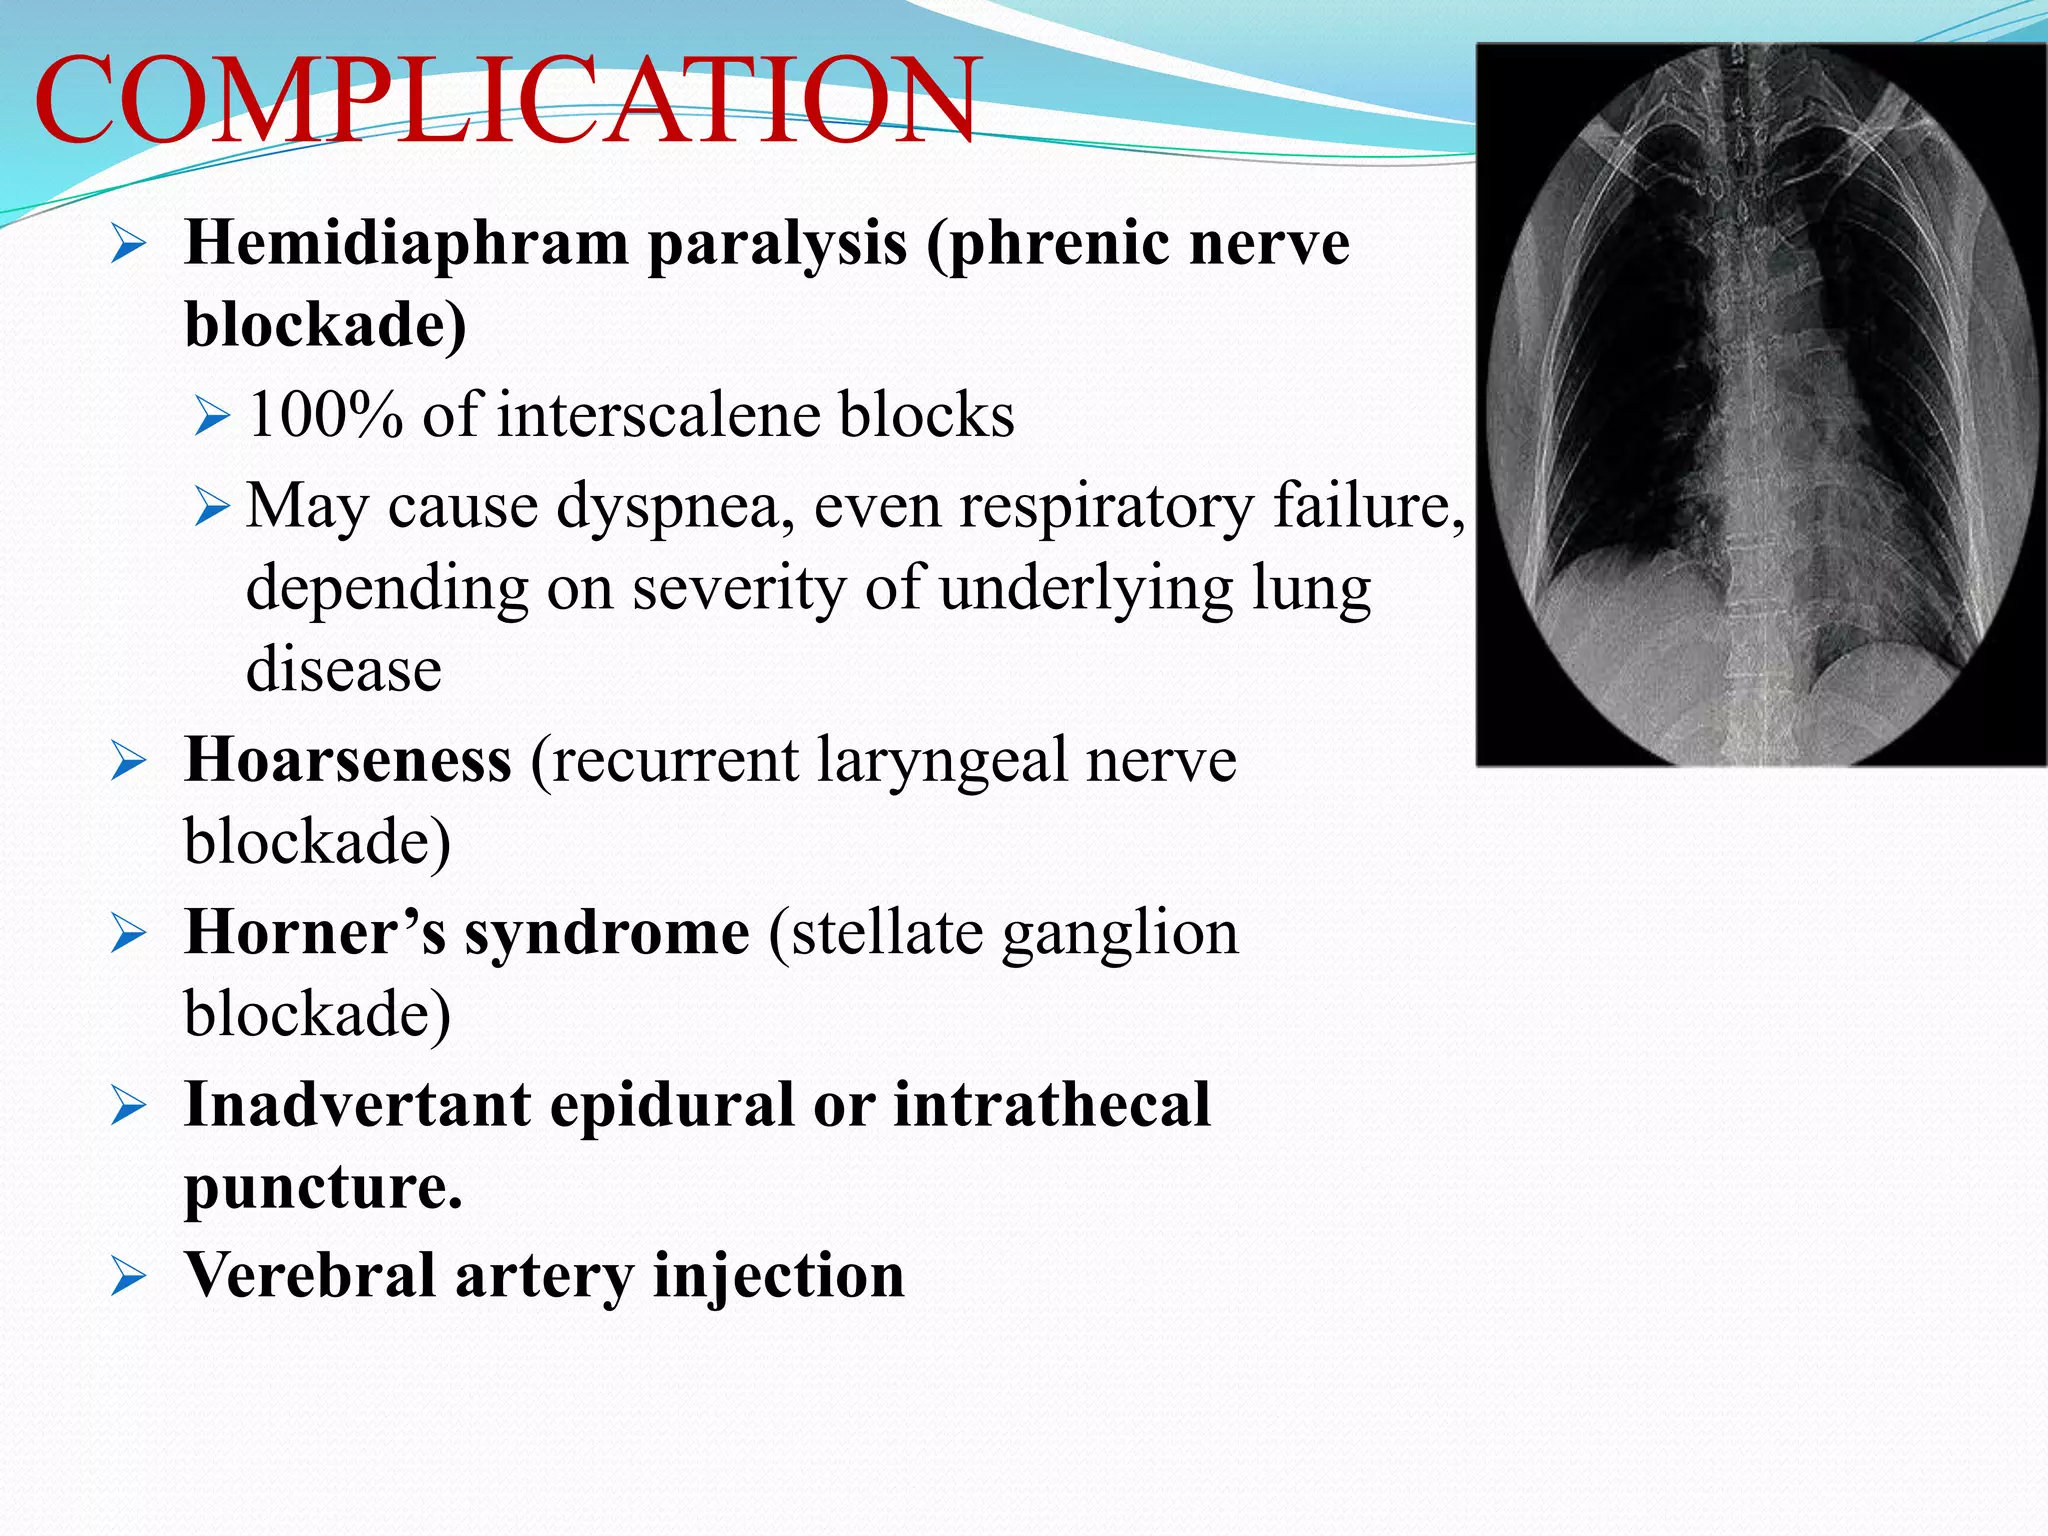

This document provides an overview of brachial plexus anatomy and techniques for brachial plexus nerve blocks. It begins with a description of the brachial plexus formation from cervical and thoracic nerve roots and its branching pattern. Four main approaches for brachial plexus nerve blocks are described: interscalene, supraclavicular, infraclavicular, and axillary. Details are provided on the anatomy and techniques for performing interscalene and supraclavicular brachial plexus blocks. Ultrasound guidance is discussed as an advancement which allows real-time visualization of needle and nerve. Complications are also summarized.